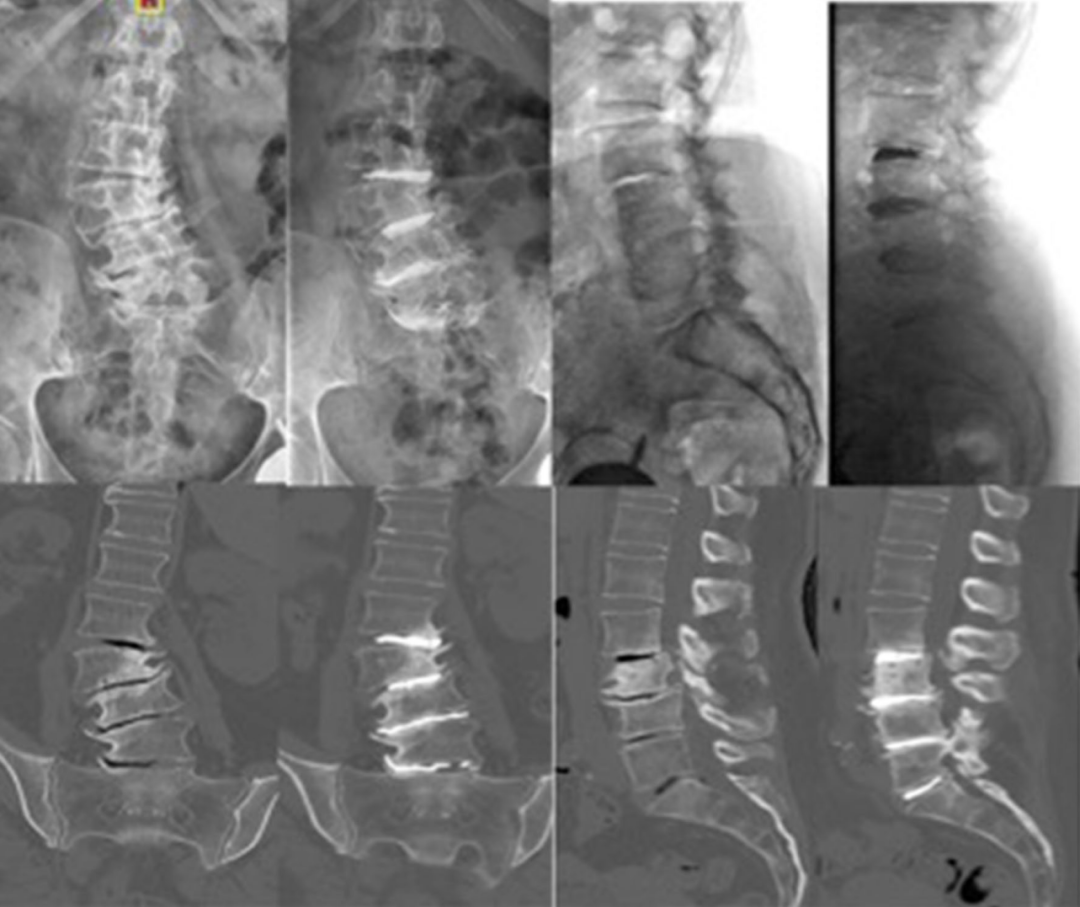

回顾性分析28例(112椎间盘)单节段或多节段PCD治疗严重腰椎间盘退变引起的轴性腰痛和功能障碍的临床资料。全部采用全麻,经Kambin三角椎间盘造影入路注入高粘度PMMA骨水泥。

术后骶骨倾斜角和骨盆倾斜角均明显减小,腰椎节段和整体前凸角、椎间盘和椎间孔高度均明显增加。随访6个月,VAS和ODI评分较术前显著改善,且腰痛的改善程度与节段性侧凸矫正明显相关,且无明显并发症的发生。

最后,作者得出结论,PCD是一种治疗严重椎间盘退变引起轴性腰痛和功能障碍的有效微创方法,不但可纠正腰椎侧凸,而且可达到椎间孔间接减压的效果。对于伴有多种内科疾病且不宜行开放手术的老年患者,PCD是一种选择。